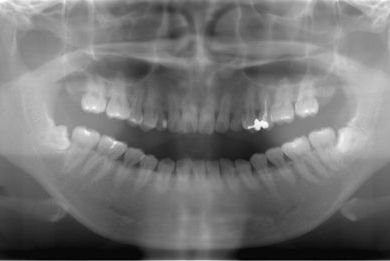

治療前

• 治療前